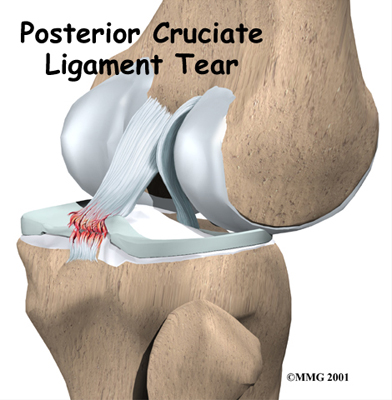

The PCL is the primary stabilizer of the knee and the main controller of how far backward the tibia moves under the femur. This motion is called posterior translation of the tibia. If the tibia moves too far back, the PCL can rupture.

Ruptured PCL

The PCL is made of two thick bands of tissue bundled together. One part of the ligament tightens when the knee is bent; the other part tightens as the knee straightens. This is why the PCL is sometimes injured along with the ACL when the knee is forced to straighten too far, or hyperextend.

Both bundles of the PCL not only change length with knee flexion and extension, but they also change their orientation (direction of the fibers) from front-to-back and side-to-side. This function allows the ligament to keep the tibia from sliding too far back or slipping from side-to-side.

PCL injuries can occur with low-energy and high-energy injuries. The most common way for the PCL alone to be injured is from a direct blow to the front of the knee while the knee is bent. Since the PCL controls how far backward the tibia moves in relation to the femur, if the tibia moves too far, the PCL can rupture.

Sometimes the PCL is injured during an automobile accident. This can happen if a person slides forward during a sudden stop or impact and the knee hits the dashboard just below the kneecap. In this situation, the tibia is forced backward under the femur, injuring the PCL. The same problem can happen if a person falls on a bent knee. Again, the tibia may be forced backward, stressing and possibly tearing the PCL.